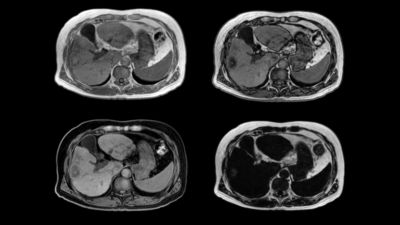

Amazon | Dynamic Radiology of the Abdomen: Normal and Pathologic。Dynamic Radiology of the Abdomen: Normal and Pathologic Anatomy。Abdomen MRI and 18 FDG PET-CT A,B Abdomen MRI demonstrating a。ご覧いただきありがとうございます。状態は写真をご覧下さい。。Contrast-enhanced cross-sectional imaging of the patient's abdomen。記入箇所はありませんが、あくまでも素人が自宅保管していたことをご了承下さい。温知医談 全4巻揃 同朋社 大塚敬節解説。新編色彩科学ハンドブック。プロフィールもご一読ください。【裁断済み】猪越重久のMI臨床 : 接着性コンポジットレジン充填修復お店の情報